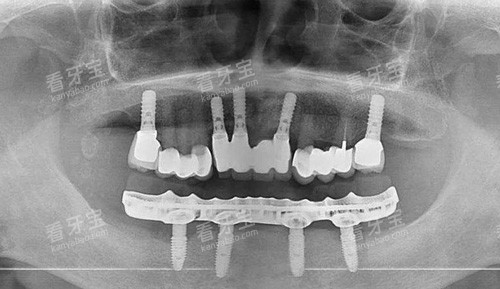

全口吸附性义齿是一种采用特殊设计的修复体,通过功能性印模技术和边缘封闭系统,在口腔内形成稳定的负压吸附力,使假牙能够紧密贴合牙槽骨黏膜表面。与传统活动假牙相比,它的稳固性和舒适度都有显著提升,外观也更接近自然牙齿。

对于一些特殊情况,如重度牙槽嵴萎缩或颌弓形态异常,可能需要特殊设计的义齿,价格也会相应调整:

重度牙槽嵴萎缩方案

钛合金加强型全口:26000元起